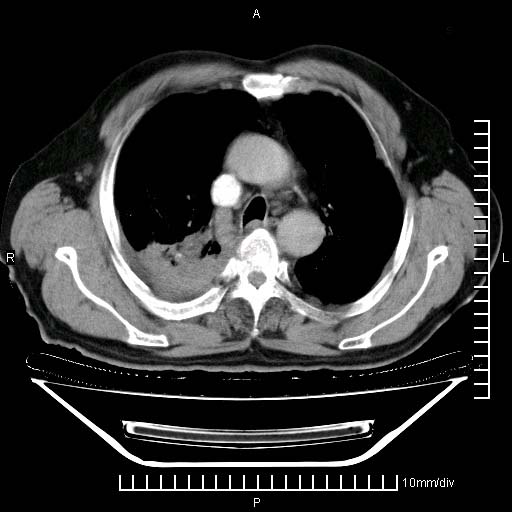

标题: CT24043:胸部增强:男性,60岁

既往肺结核,近10几天,咳嗽,咳痰,右侧胸痛,疼痛较明显,右上肺斑块考虑结核灶胸膜粘连,增强,可惜动脉期没有定好,未见强化,可延迟4分后又见较明显强化,中心见低密度影,如果说结核是边缘强化,可这个灶强化的面积挺大的,让人很挠头。

1)两肺继发性肺结核。2)右侧胸膜增厚+少量胸腔积液。